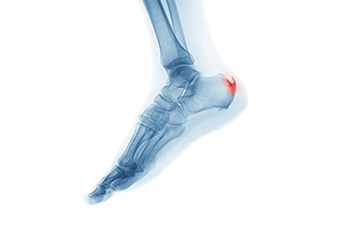

Symptoms of gout are warmth, swelling, discoloration, and tenderness in the affected joint area. The small joint on the big toe is the most common place for a gout attack to occur.

Gout is a form of arthritis that is characterized by sudden, severe attacks of pain, redness, and tenderness in the joints. The condition usually affects the joint at the base of the big toe. A gout attack can occur at any random time, such as the middle of the night while you are asleep.

- Intense Joint Pain – Usually around the large joint of your big toe, and it most severe within the first four to twelve hours

- Inflammation and Redness -Affected joints may become swollen, tender, warm and red